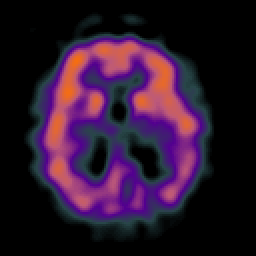

Alzheimer's disease: Perfusion SPECT -- Slice #29

[Home][Help][Clinical][Tour 1][Tour 2] Slice 29